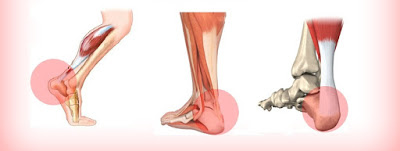

1.足弓處拉扯.緊繃.甚至撕裂的感覺(星星記號處)

2.足跟後側疼痛(阿基里斯腱肌腱炎)

1.小腿二頭肌拉筋放鬆,原因如下

所以利用傾斜板拉筋,放鬆小腿不是沒有原因(傾斜角度因人而異,不能過度)